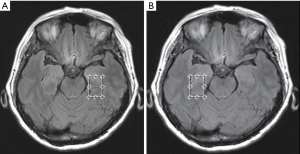

Conventional MRI scans were obtained by a standard 8-channel head coil using a 3.0 T GE MRI Systems (Signa HDx Twin speed; GE Medical, Milwaukee, Wisconsin, USA). Host scanning was then changed from the clinical mode to research mode. Under this mode, axial T2 fluid attenuated inversion recovery images were used for performing spectroscopic acquisition. To ensure the same locations for each participant, the volume of interests (VOIs) for the 1H-MRS spectra were assigned to a total of 16 brain regions, as shown in Figure 1A,B and Figure 2 including the bilateral hippocampus (Hip), precuneus (Pr), posterior cingulate cortex (PCC), white matter of occipital lobe (OLWM), dorsal thalamus (DT), lenticular nucleus (LN), caput nuclei caudati (CNC), and white matter of frontal lobe (FLWM) for further metabolite quantification. Since each participant’s head size differs, the brain structure is also slightly different. To minimize the impact of cerebrospinal fluid (CSF) contamination, skull bone and air on the metabolite concentration, the VOI acquisitions were determined based on the anatomical landmarks of each participant. Owing to poor shimming on the basicranial level due to the tissue-air interface near the petrous bone, a fully automated point-resolved spectroscopy (PRESS, Probe-P) pulse sequence was used to obtain single-voxel proton MRS data (1H-SVS, TE/TR =35/1,500 ms, NEX: 4, phase × frequency: 1×1) for the bilateral Hip. The SVS VOIs were average in size 3.00 cm3 [1.0 cm (width) × 2.0 cm (length) × 1.5 cm (thickness)]. Two-dimensional multi-voxel proton MRS with PRESS pulse sequence (FOV: 16.0 cm × 16.0 cm; TE/TR =35/1,500 ms, NEX: 1, phase × frequency: 18×18) was performed at the basal ganglia level to acquire the multi-voxel MRS data. The VOIs of the multi-voxel section was about 8.0 cm (left to right) × 10.0 cm (anterior to posterior) ×1.5 cm (thickness). Thus, every single average VOI was 1.19 cm3 [(FOV: 16.0 cm × 16.0 cm/phase, frequency: 18×18) ×1.5 cm]. The VOI size and signal-to-noise ratio (S/N) in the left and right brain hemispheres of the three groups are shown in Table S1 and Table S2. Automatic prescan procedures such as calibration, shimming, and chemical shift selective water suppression were optimized as a concentration reference for the VOIs. The acquisition time of the 1H-SVS on each side of Hip were 3 minutes 42 seconds and the acquisition time of the 1H-MVS on basal ganglia slice were 8 minutes 12 seconds.

Compared with ECs group, SCD plus individuals were observed to have significantly reduced NAA levels in the left Hip, left PCC, left Pr and left CNC. mI value was only found elevated in the right Hip. The NAA/mI ratio decreased in the left Hip, left PCC, left Pr, left OLWM, and right Hip. The concentration of Cho was observed to only increase in the right PCC. Figure 3 shows an example images of increased Cho levels in the right PCC in patients with SCD plus, while no significant difference was observed in the left PCC.